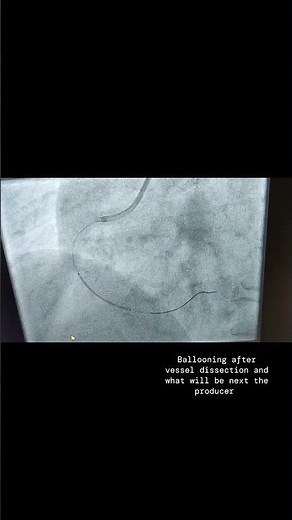

Cath Lab - PCI

Cardiac Cath